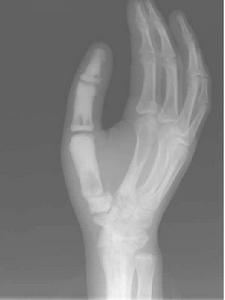

可以無症狀。有些病人身材矯小,發育延遲,容易發生骨折,且癒合緩慢。但不發生畸形連線,這與成骨不全症不同。顱骨硬化,致腦積水及顱神經受壓,導致眼萎縮、面癱、失聽等。副鼻竇腔隙變少,閉塞、引流不暢而致副鼻竇炎。貧血約占30%,重者可以致命,常伴有代嘗性脾、肝及淋巴結腫大。易發生齲齒,導致下頜骨骨髓炎。有些病人可見雞胸及串珠肋。X線表現特徵為骨骼濃厚緻密,失去其原有結構,無法區分皮質及髓腔,兩端膨大呈杵狀。有的患嬰在子宮內已有如此表現。全身大多數骨均可累及,但下頜骨少見。由於骨硬化過程可以變緩或暫停,因此,在骨骼上可見到有深淺不同的橫紋。骨骺亦緻密,有時可見呈同心圓狀。椎體的上、下兩端緻密,但中間有一條骨質正常的帶,常被形容為“夾心麵包椎體”。顱骨亦硬化,氣竇消失,垂體窩變淺,鞍背突增生,顱窩變狹,顱孔縮小。

本病突出的x線改變為廣泛性骨硬化,骨呈無結構的密度增高,骨小梁影像消失,可累及全身或大部骨骼。其易發部位為脊柱、骨盆、肋骨、顱骨、脛腓骨及手足的短管狀骨。患者骨密度顯著增加,皮質增厚,髓腔變窄甚至閉塞。病變呈對稱性分布,小兒期即可顯示病變,重者未出生前子宮內即可發現。

(4)長骨:病變起始於乾骺端,漸向骨幹發展。常可見到深淺交替的波浪狀橫紋。同樣病變也可見於掌、跖、指、趾諸骨,在靠近骨骺一端較為明顯。

X線表現:基本X線表現廣泛均勻,骨密度增高硬化,骨小梁變粗、模糊,皮質增厚,髓腔狹窄,甚至消失。本院曾有3例石骨症病人,因發生骨折,欲行帶鎖髓內針固定,因髓腔消失,骨質硬化,改用鋼板或動力髁鋼板固定,骨密度增高有明顯的均勻對稱性,以四肢、肋骨和骨盆較明顯。骨中骨主要見於掌指、跖趾關節及肋骨等,骨中骨表現為邊界比較明顯的緻密骨島。夾心椎又名夾心蛋糕征,其形成是由於椎體上下軟骨板富含血管,在鈣吸收不足的情況,該部類骨質沉積過多。類骨質對破骨細胞具有明顯的抑制作用,而椎體中部缺乏這種類骨質,故而被破骨細胞侵蝕,形成椎上下高密度而中間低密度,形如三明治樣。髂骨翼年輪樣改變。射線可透過帶是較正常骨區域,而緻密帶存在大量不起作用的破骨細胞。顱骨穹窿顱底均增厚硬化,以顱底骨質增生最明顯。

本病X線表現具有特徵性,其特徵為骨骼濃厚緻密,失去其原有結構,無法區分皮質及髓腔,兩端膨大呈杵狀。有的患嬰在子宮內已有如此表現。全身大多數骨均可累及,但下頜骨少見。由於骨硬化過程可以變緩或暫停,因此,在骨骼上可見到有深淺不同的橫紋。骨骺亦緻密,有時可見呈同心圓狀。椎體的上、下兩端緻密,但中間有一條骨質正常的帶,常被形容為“夾心麵包椎體”。顱骨亦硬化,氣竇消失,垂體窩變淺,鞍背突增生,顱窩變狹,顱孔縮小。

石骨症為全身性骨骼受累的疾病,顱骨的X線表現為硬化,尤以顱底為顯著,特別是蝶骨體及大、小翼均明顯改變。蝶鞍大小正常或縮小,床突、鞍底皆硬化。顳骨及枕骨也可硬化,使板障封閉,失去三層的分野。頂骨額骨及顏面骨可不受侵犯或僅有輕微變化。視神經孔變窄且邊緣模糊乳突小房及鼻旁竇變小或發育不全石骨症在長管狀骨及脊椎有特徵性的X線改變。脊椎椎體表現為上下緣特别致密,其間密度低者為正常骨質,組成三層帶狀影。長管狀骨表現為“骨內骨”,骨質緻密髓腔變窄或消失於乾骺部顯示多條互為平行或呈波狀緻密線紋,乾骺部可呈杵狀變形,尤其脛骨上端內側可表現為邊緣不整呈粗鋸齒改變,髂骨翼典型改變為平行髂嵴,的多層的同心弧狀硬化帶此外,肋骨和鎖骨均可呈均勻硬化。有時還可見到骨折,於掌、蹠、指及趾骨常有界限分明的骨島出現。